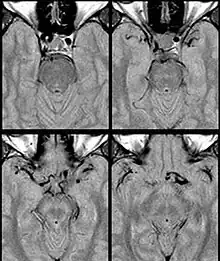

Fig. 1: Dolichoectasia of the suprasellar segment of the left internal carotid artery with compression of the optic chiasm

Internal carotid artery dolichoectasia is particularly interesting because the artery normally already contains one hairpin turn. Seen in an MRI as two individual arteries at this hairpin, a carotid artery dolichoectasia can progress so far as to produce a second hairpin turn and appear as three individual arteries on an MRI. In the case of a dolichoectasia of the Internal Carotid Artery (ICD), the pathogenesis is primarily related to compression of the optic nerves at the optic chiasma (see Fig. 1 and 2).